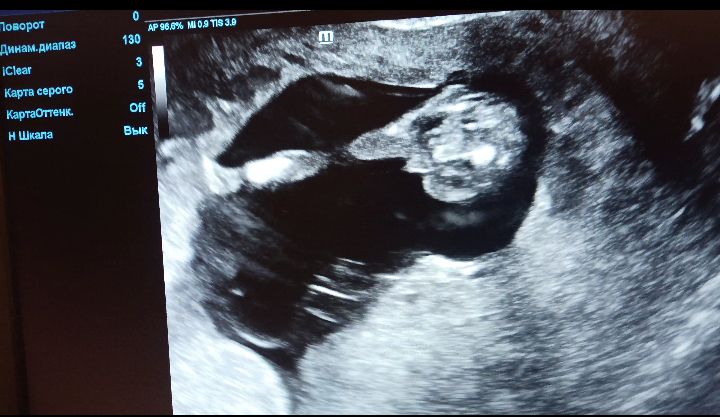

Машуля, ))))) это малыш попой сидит одну ножку видно ,а вторую нет ,а вот между ножек то ли мальчик ,то ли ,как мне где сказали ,что у девочек тоже может слипнутся на этом сроке ))) сомнительно ,но вот вдруг )))))))

Снизу будто мальчик) а есть фото сбоку?

Девочки подскажите мне или писюнь))? 14 недель по узи По УЗИ - девочка?